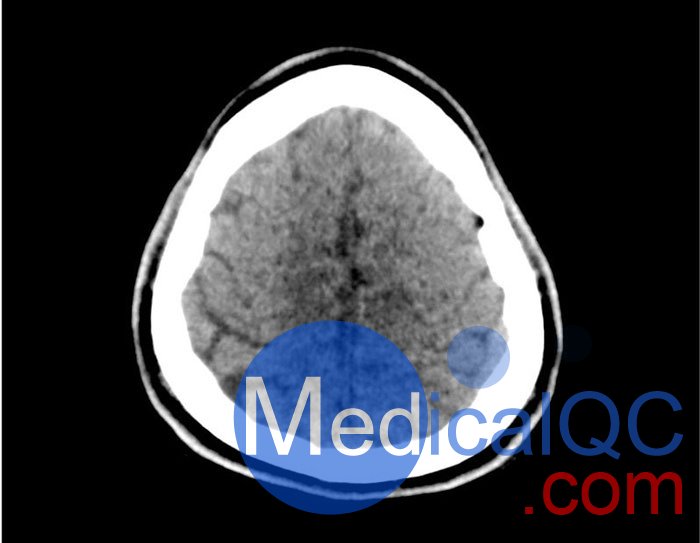

50-01頭部CT模體,50-01腦中風(fēng)頭部模體,50-01腦出血頭部模體規(guī)格

大?。?約 190 x 210 x 147 mm

重量: 約 2640 g

基材: 纖維素-聚合物復(fù)合材料

最佳管電壓: 120 kVp – 可根據(jù)要求進(jìn)行調(diào)整

產(chǎn)品應(yīng)用:器官分割、圖像質(zhì)量?jī)?yōu)化、中風(fēng)、顱內(nèi)出血

診斷功能:梗塞、出血、血管病變、球形病變

50-01頭部CT模體,50-01腦中風(fēng)頭部模體,50-01腦出血頭部模體影像效果圖: